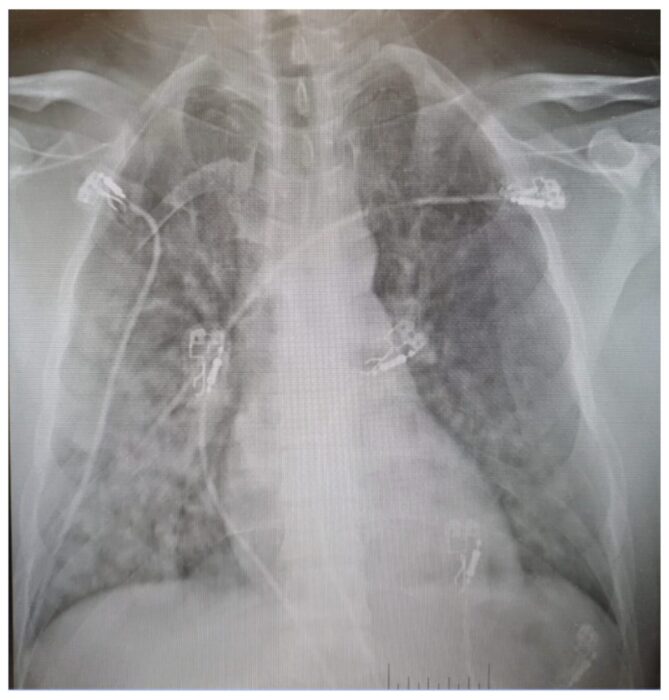

A chest X-ray led doctors to diagnose high-altitude pulmonary edema, a life-threatening condition in which low oxygen at altitude increases pressure in the lung’s blood vessels, causing fluid to leak into the air spaces and impair the exchange of oxygen into the blood.

The technician’s X-ray. Bases in Antarctica have some advanced medical facilities, but they are limited. Photo: Larcher et al. 2026